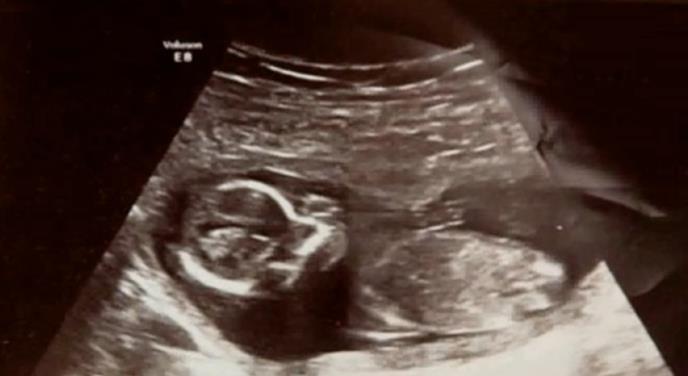

(VIDEO) DOKTORI SU BILI U ŠOKU: 10 dana posle pobačaja čuli su bebine otkucaje srca...

Majkl i Rouz iz Irske imali su dvoje dece kada su saznali da je Rouz u drigom stanju. Bili su presrećni i jedva su čekali novog člana porodice.

Njihova sreća nije dugo trajala. U sedmoj sedmici trudnoće, osetila je oštar bol i primetila je krv. Sa svojim suprugom je otišla u bolnicu i tako su joj potvrdili njene sumnje.

Nekoliko rezultata je pokazalo da je izgubila bebu. Majkl i Rouz su bili tužni kao nikada. Lečnici su joj dali dve tablete koje se koriste za pobačaj, kako bi "očistila" svoju maternicu i sprečila infekcije. Sledećeg dana je Majkl zašla iz bolnice.

Njen prijatelji su joj pružili utehu i rekli joj da ponovo uradi test trudnoće, kako bi proverila da li uvek ima ostatke trudnoće. Test je bio pozitivan, i usledeo je šok...